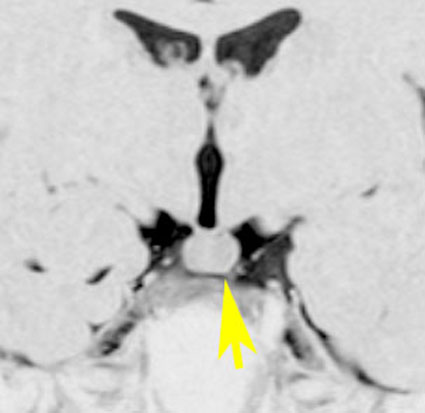

乳頭体(矢印)からは離れているタイプです。ですから笑い発作を生じません。右側のガドリニウム増強画像ではまったく増強されていないのが特徴です。

この例は珍しいのですが,橋 ponsにも茎 pedicleを有するタイプです。